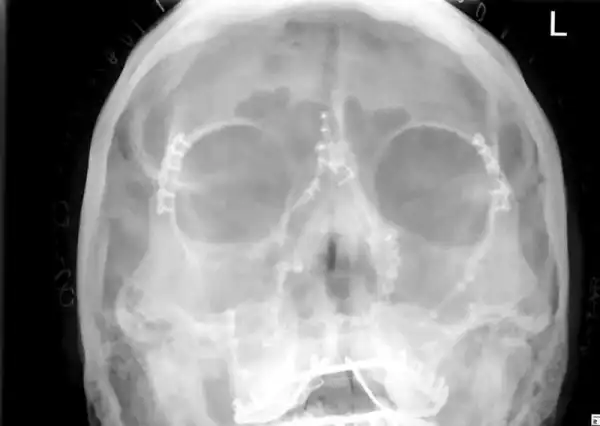

38-летняя педиатр Элизабет Калтон угодила под копыта испугавшейся лошади, в результате чего ее лицо превратилось в месиво. В ходе 10-часовой операции хирург восстановил череп пострадавшей, установив десяток металлических пластин и четыре десятка шурупов. Судя по снимкам Элизабет с врачом, результатом операции она довольна.